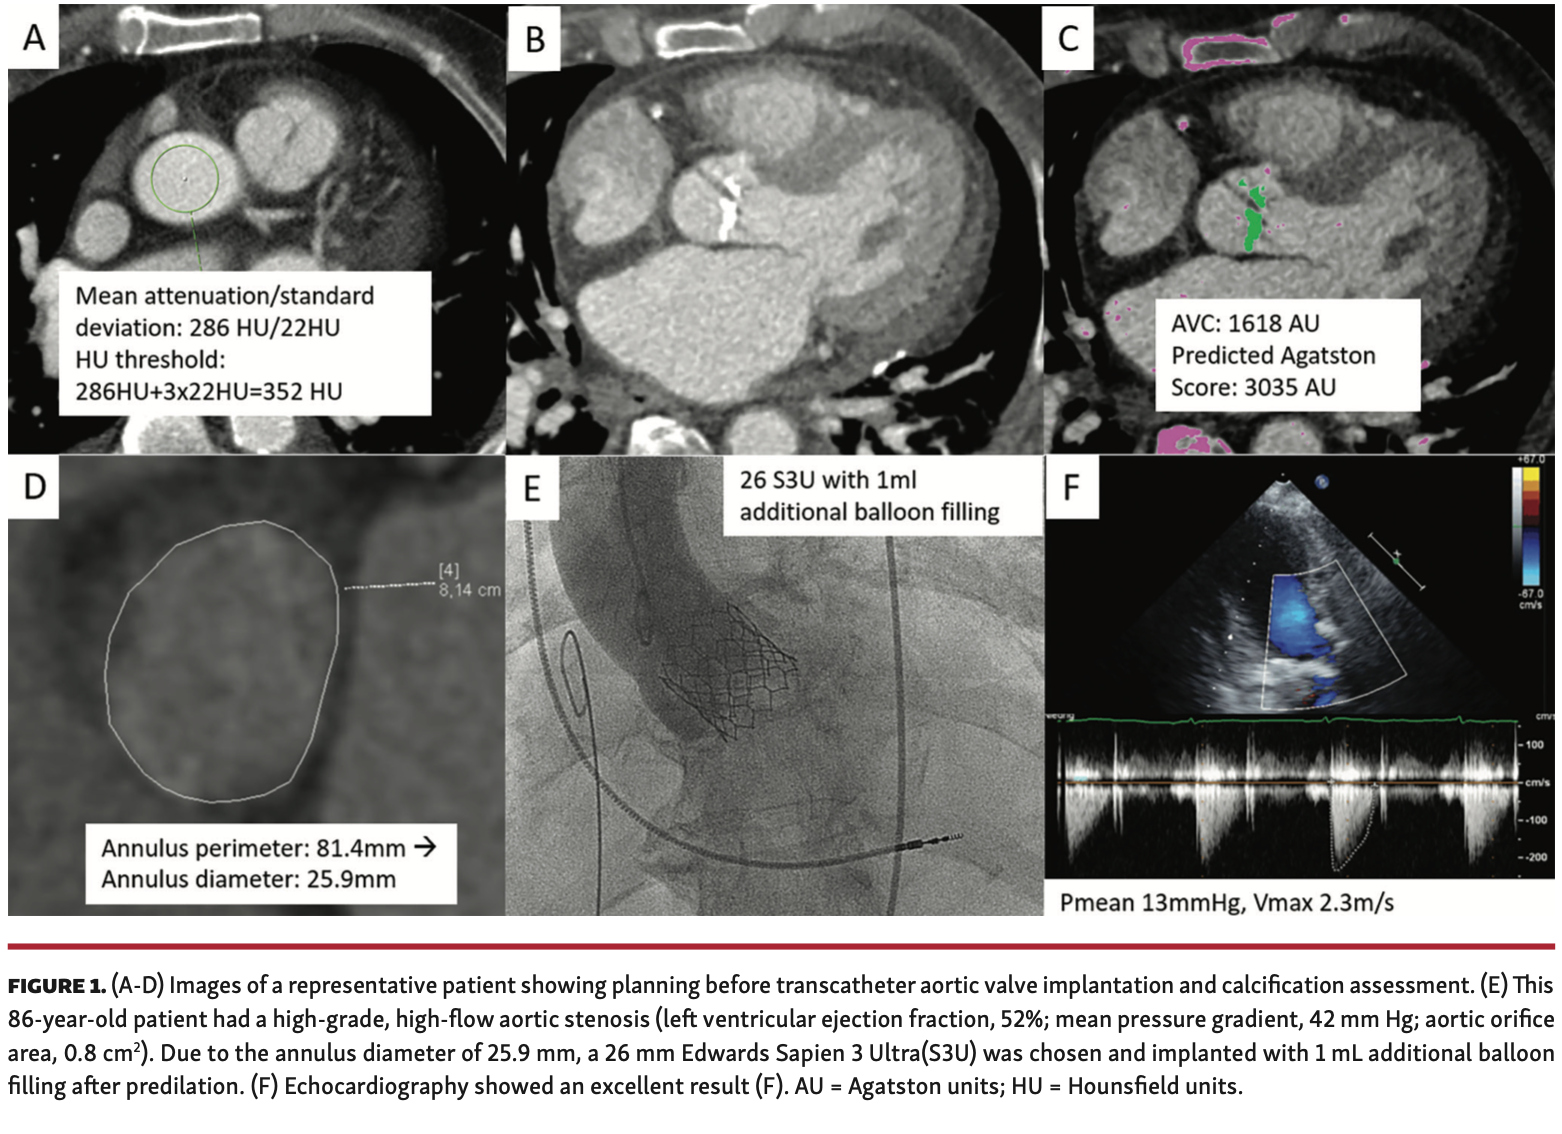

The patient cohort was representative of a typical TAVI cohort, with a mean age of 82 ± 6 years and mean EuroSCORE II of 4.3% (Table 1). Quantification of aortic valve and left ventricular outflow tract calcification revealed a median Agatston score of 2571 AU (IQR, 1685-3467 AU) for the aortic valve and 112 AU (IQR, 11-293 AU) for the left ventricular outflow tract (Figure 1). The annular sizes were 19.7 mm, 22.9 ± 0.2 mm, and 25.8 ± 0.2 mm, respectively, for the 20 mm S3U device (n = 1 patient), 23 mm S3U (n = 18 patients), and 26 mm S3U device (n = 11 patients). In all 30 patients, the S3U was implanted without any procedural complications. Balloon valvuloplasty was performed before TAVI in 26 of the 30 patients with commercially available balloons. The decision for an increased balloon filling during TAVI was made in 23 of the 30 patients, as described previously for the Edwards Sapien 3 valve (Table 2).5 Postdilation was performed in 4 of the 30 patients (13%). Immediate postprocedural aortography revealed an excellent result in 25 patients (83%) and grade I aortic insufficiency in 5 patients (17%). Postprocedural transthoracic echocardiography (2-3 days after TAVI) showed an excellent result in all but 2 patients. Aortic insufficiency grade I was seen in the latter. Thirty-day outcome was successfully assessed in all 30 patients. Thirty-day survival rate was 96.7%; 1 patient passed away at day 8 post TAVI due to an unexpected arterial bleeding complication at the access site.